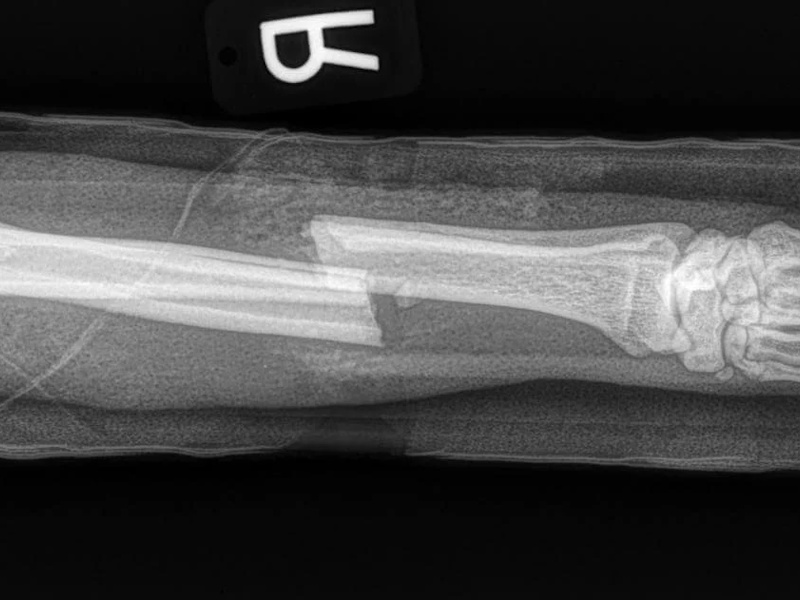

Fore Limb (Humerus, Radius/Ulnar, Metacarpus)

Hind Limb (Pelvis, Femur, Patella, Tibia/Fibula, Lateral Malleolus)